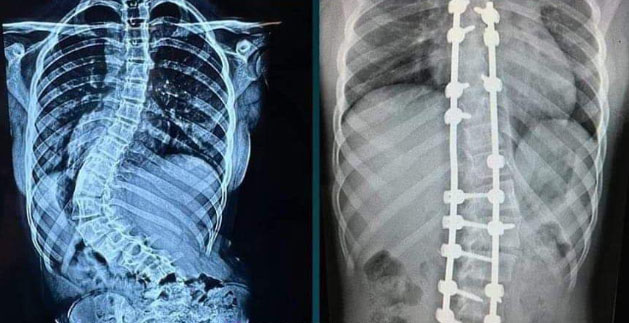

Agatha havia sido diagnostica em 2021 com um tipo grave de escoliose e tinha uma curvatura da coluna em forma de “S” e que já comprometia alguns órgãos da garota.

A família chegou a vender bolos para conseguir pagar a cirurgia que inicialmente custaria R$ 150 mil. Mas, como o problema se agravou (a escoliose idiopática passou de 75 para 101 graus), o procedimento iria custar R$ 250 mil.

A campanha teve repercussão nacional e sensibilizou o médico Luciano Miller, especialista em coluna do Hospital Albert Einstein, que decidiu realizar o procedimento de graça, que ocorreu no dia 20 de março do ano passado.